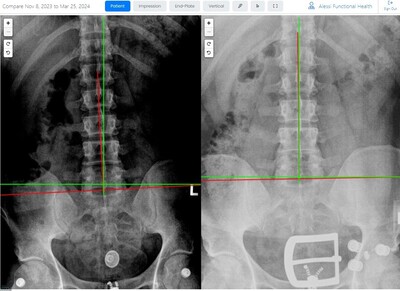

Results You Can See... and Feel!